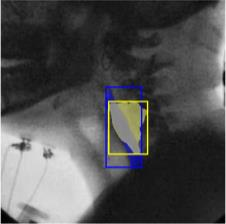

The videofluoroscopic swallowing study (VFSS) is a gold-standard imaging technique for assessing swallowing, but analysis and rating of VFSS recordings is time consuming and requires specialized training and expertise. Researchers have recently demonstrated that it is possible to automatically detect the pharyngeal phase of swallowing and to localize the bolus in VFSS recordings via computer vision, fostering the development of novel techniques for automatic VFSS analysis. However, training of algorithms to perform these tasks requires large amounts of annotated data that are seldom available. We demonstrate that the challenges of pharyngeal phase detection and bolus localization can be solved together using a single approach. We propose a deep-learning framework that jointly tackles pharyngeal phase detection and bolus localization in a weakly-supervised manner, requiring only the initial and final frames of the pharyngeal phase as ground truth annotations for the training. Our approach stems from the observation that bolus presence in the pharynx is the most prominent visual feature upon which to infer whether individual VFSS frames belong to the pharyngeal phase. We conducted extensive experiments with multiple convolutional neural networks (CNNs) on a dataset of 1245 bolus-level clips from 59 healthy subjects. We demonstrated that the pharyngeal phase can be detected with an F1-score higher than 0.9. Moreover, by processing the class activation maps of the CNNs, we were able to localize the bolus with promising results, obtaining correlations with ground truth trajectories higher than 0.9, without any manual annotations of bolus location used for training purposes. Once validated on a larger sample of participants with swallowing disorders, our framework will pave the way for the development of intelligent tools for VFSS analysis to support clinicians in swallowing assessment.